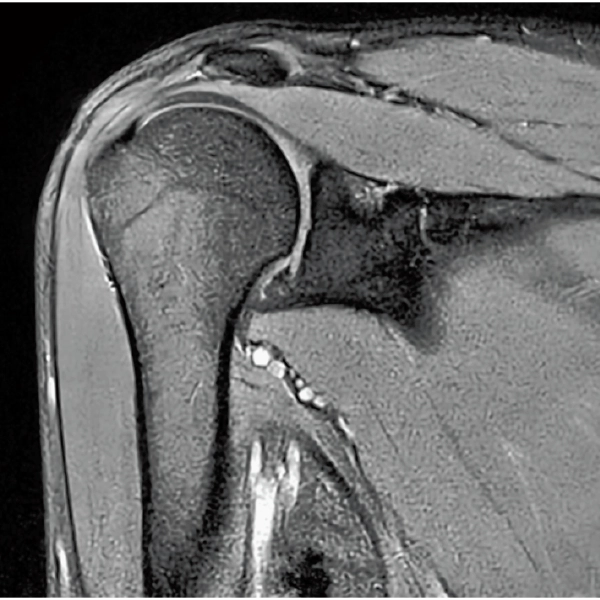

DLR offers 2 options

High Resolution

T2WI, 0.56×0.70×3.0mm, 2:28